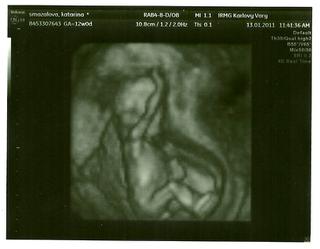

My sme boli vcera na screeningu prveho trimestru. Drobecek ma uz 6,8 cm od hlavicky po prdeklu a z nozickami ma 12 cm. Tak sme boli v soku aky je uz velky. Vsetko je v poriadku, uz mi vysadili vsetky lieky, za co som velmi rada, lebo som z nich uz mala traviace problemy. A este sme sa dozvedeli, ze nie sme na konci 12tt, ale na konci 13tt, lebo sa to pocita od dna punkce. A my sme mysleli, ze od dna transferu. A bude to asi chlapecek 😀 lebo ten geneticky vyrastko je vraj daky velky.A este jedna sranda, spi tak isto ako manzelik, z rucickou pod hlavou.Prikladam foto